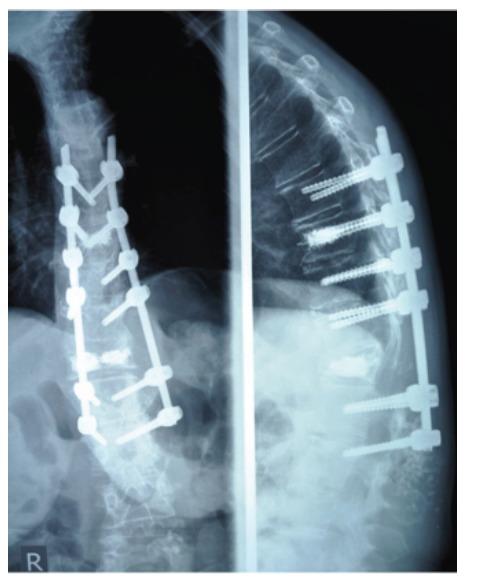

Previous studies on spinal surgery in PD patients report an exceptionally high rate of complications. Failure and re -operation are frequent outcomes. This is a retrospective case series with the aim of establishing the rate of complications in patients with concomitant Parkinson's disease. Ten patients were subjected to spinal surgery from 2005 to 2009. The indications and type of operation varied. Cases of Failed Back Surgery and re-operation were sought. Follow - up was between 6 - 42 months. All 10 patients presented some clinical or radiological complication. The most common complications were screw pull - out and progressive spinal deformity. Re - operations were performed in 5 patients, while clinical and radiological results were poor in the majority of cases. Patients with Parkinson's disease have a very high complication rate and often have to undergo revision surgery. This particular group of patients should be informed of the increased risk of failure and be closely followed - up on a regular basis.

先前关于帕金森病患者脊柱手术的研究报告称并发症发生率极高。手术失败和再次手术是常见的结果。这是一项回顾性病例系列研究,旨在确定合并帕金森病患者的并发症发生率。2005年至2009年期间,有10例患者接受了脊柱手术。手术指征和类型各不相同。我们寻找了腰椎手术失败和再次手术的病例。随访时间为6至42个月。所有10例患者均出现了一些临床或影像学并发症。最常见的并发症是螺钉拔出和进行性脊柱畸形。5例患者接受了再次手术,而大多数病例的临床和影像学结果较差。帕金森病患者的并发症发生率非常高,且常常需要接受翻修手术。应告知这一特殊患者群体手术失败风险增加,并定期进行密切随访。